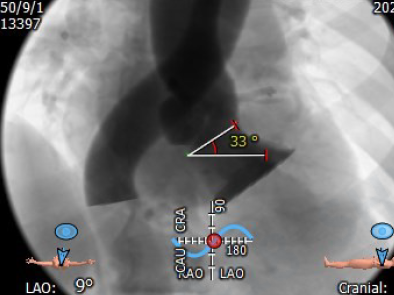

瓣环角度:33°